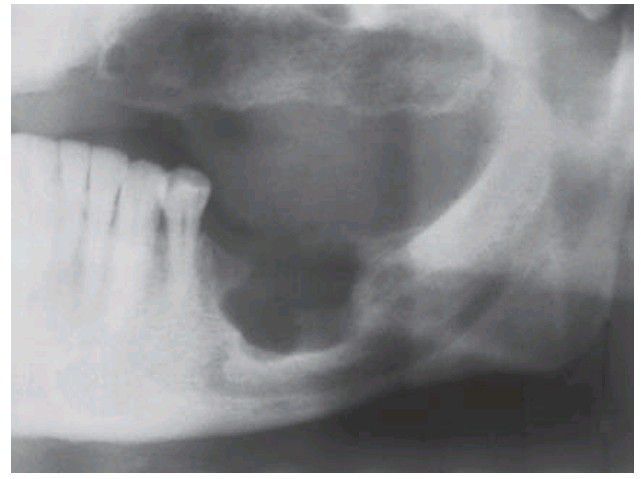

Langerhans cell histiocytosis

. This localised lesion (eosinophilic granuloma) shows the characteristic appearance of a well-defi ned radiolucency scooped out of the alveolar bone. The margin is corticated in places, but less well-defi ned elsewhere.